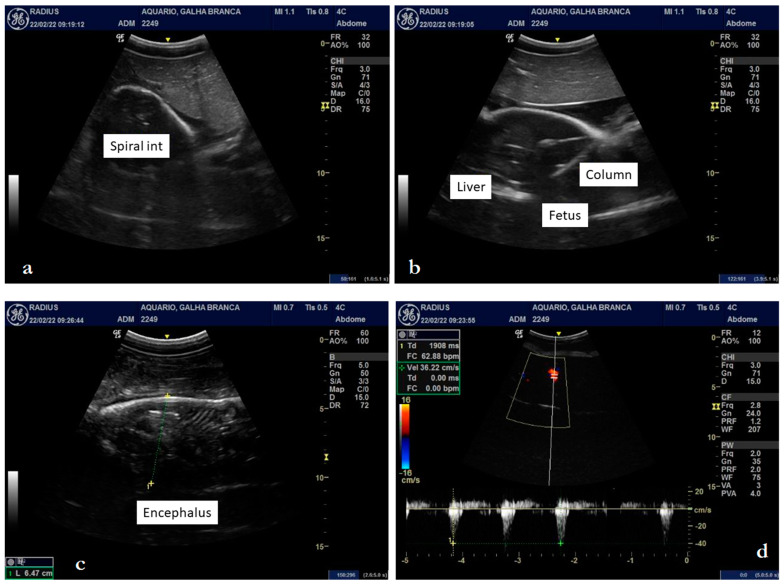

Upon ultrasound examination, it was possible to detail a fetus with a well-defined brain, tail, and pectoral and dorsal fins, with well-defined gills and coelomic cavity (Figure 1, Figure 2a–d, and Figure 3a–d). The fetal liver was characterized by a hypoechoic, homogeneous parenchyma with regular contours, also showing the gallbladder with anechogenic content (Figure 2b). The kidneys were partially defined and presented a slightly heterogeneous hypoechogenic parenchyma. The intestinal spiral with the characteristic spiral pattern was evident, as was a defined parietal stratification (Figure 3a). The cartilaginous skeleton was hyperechoic and formed a moderate posterior acoustic shadow artifact (Figure 3b). It was possible to detail the cranial conformation, define the orbital fossa housing the anechoic eyeball with a hyperechoic capsule (Figure 2c), and evaluate the biparietal diameter, which measured approximately 6.47 cm (Figure 3c).

Figure 2.

Ultrasonography of a female Triaenodon obesus (Rüppell, 1837) in late pregnancy: fetal orientation (brain/tail) and pectoral fins (a), hypoechogenic liver (b), eyes and gills (c), and heart with individualized chambers (d).

Figure 3.

Ultrasonography of a female Triaenodon obesus (Rüppell, 1837) in late pregnancy: intestinal spiral and parietal stratification (a), cartilaginous skeleton, forming a posterior acoustic shadow artifact (b), biparietal diameter of 6.47 cm (c), and cardiac blood flow of 62 beats per minute (d).

The vertebrae of the spine presented themselves as hyperechoic, individualized structures, homogeneously spaced, with an anechoic central area, possibly the spinal canal (Figure 3b). In the cross-section, the spinous processes of the vertebrae were also detailed. The gills were defined as parallel slits of alternating echogenicity (hyperechogenic and anechogenic) (Figure 2c), which, on color Doppler mapping, showed an evident signal, indicating the presence of fluid passage. The heart presented individualized chambers and an evident blood flow signal when we used the color Doppler tool (Figure 2d). With spectral Doppler, it was possible to measure the heart rate, which presented a value of 62 beats per minute at the time of the examination (Figure 3d). Considering that the average gestation period observed by Schaller [24] is 387 days and knowing that the neonate described above was born 12 days after the ultrasound examination, we calculated that it was approximately 375 days old. Therefore, the description of organogenesis by this method characterized the final third of the pregnancy.